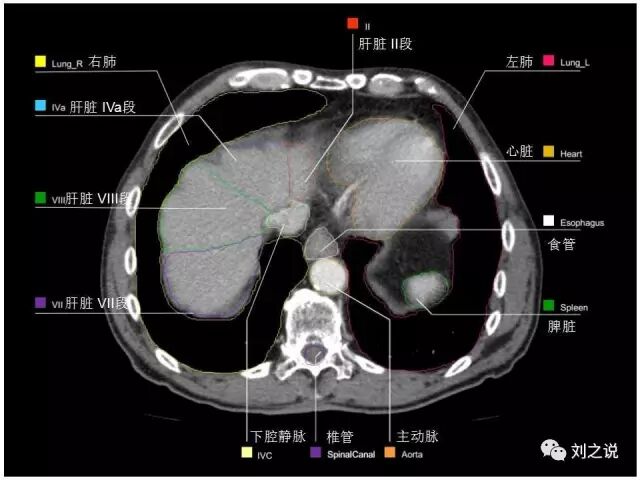

参考RTOG共识和3D-body解剖。

来源:刘之说